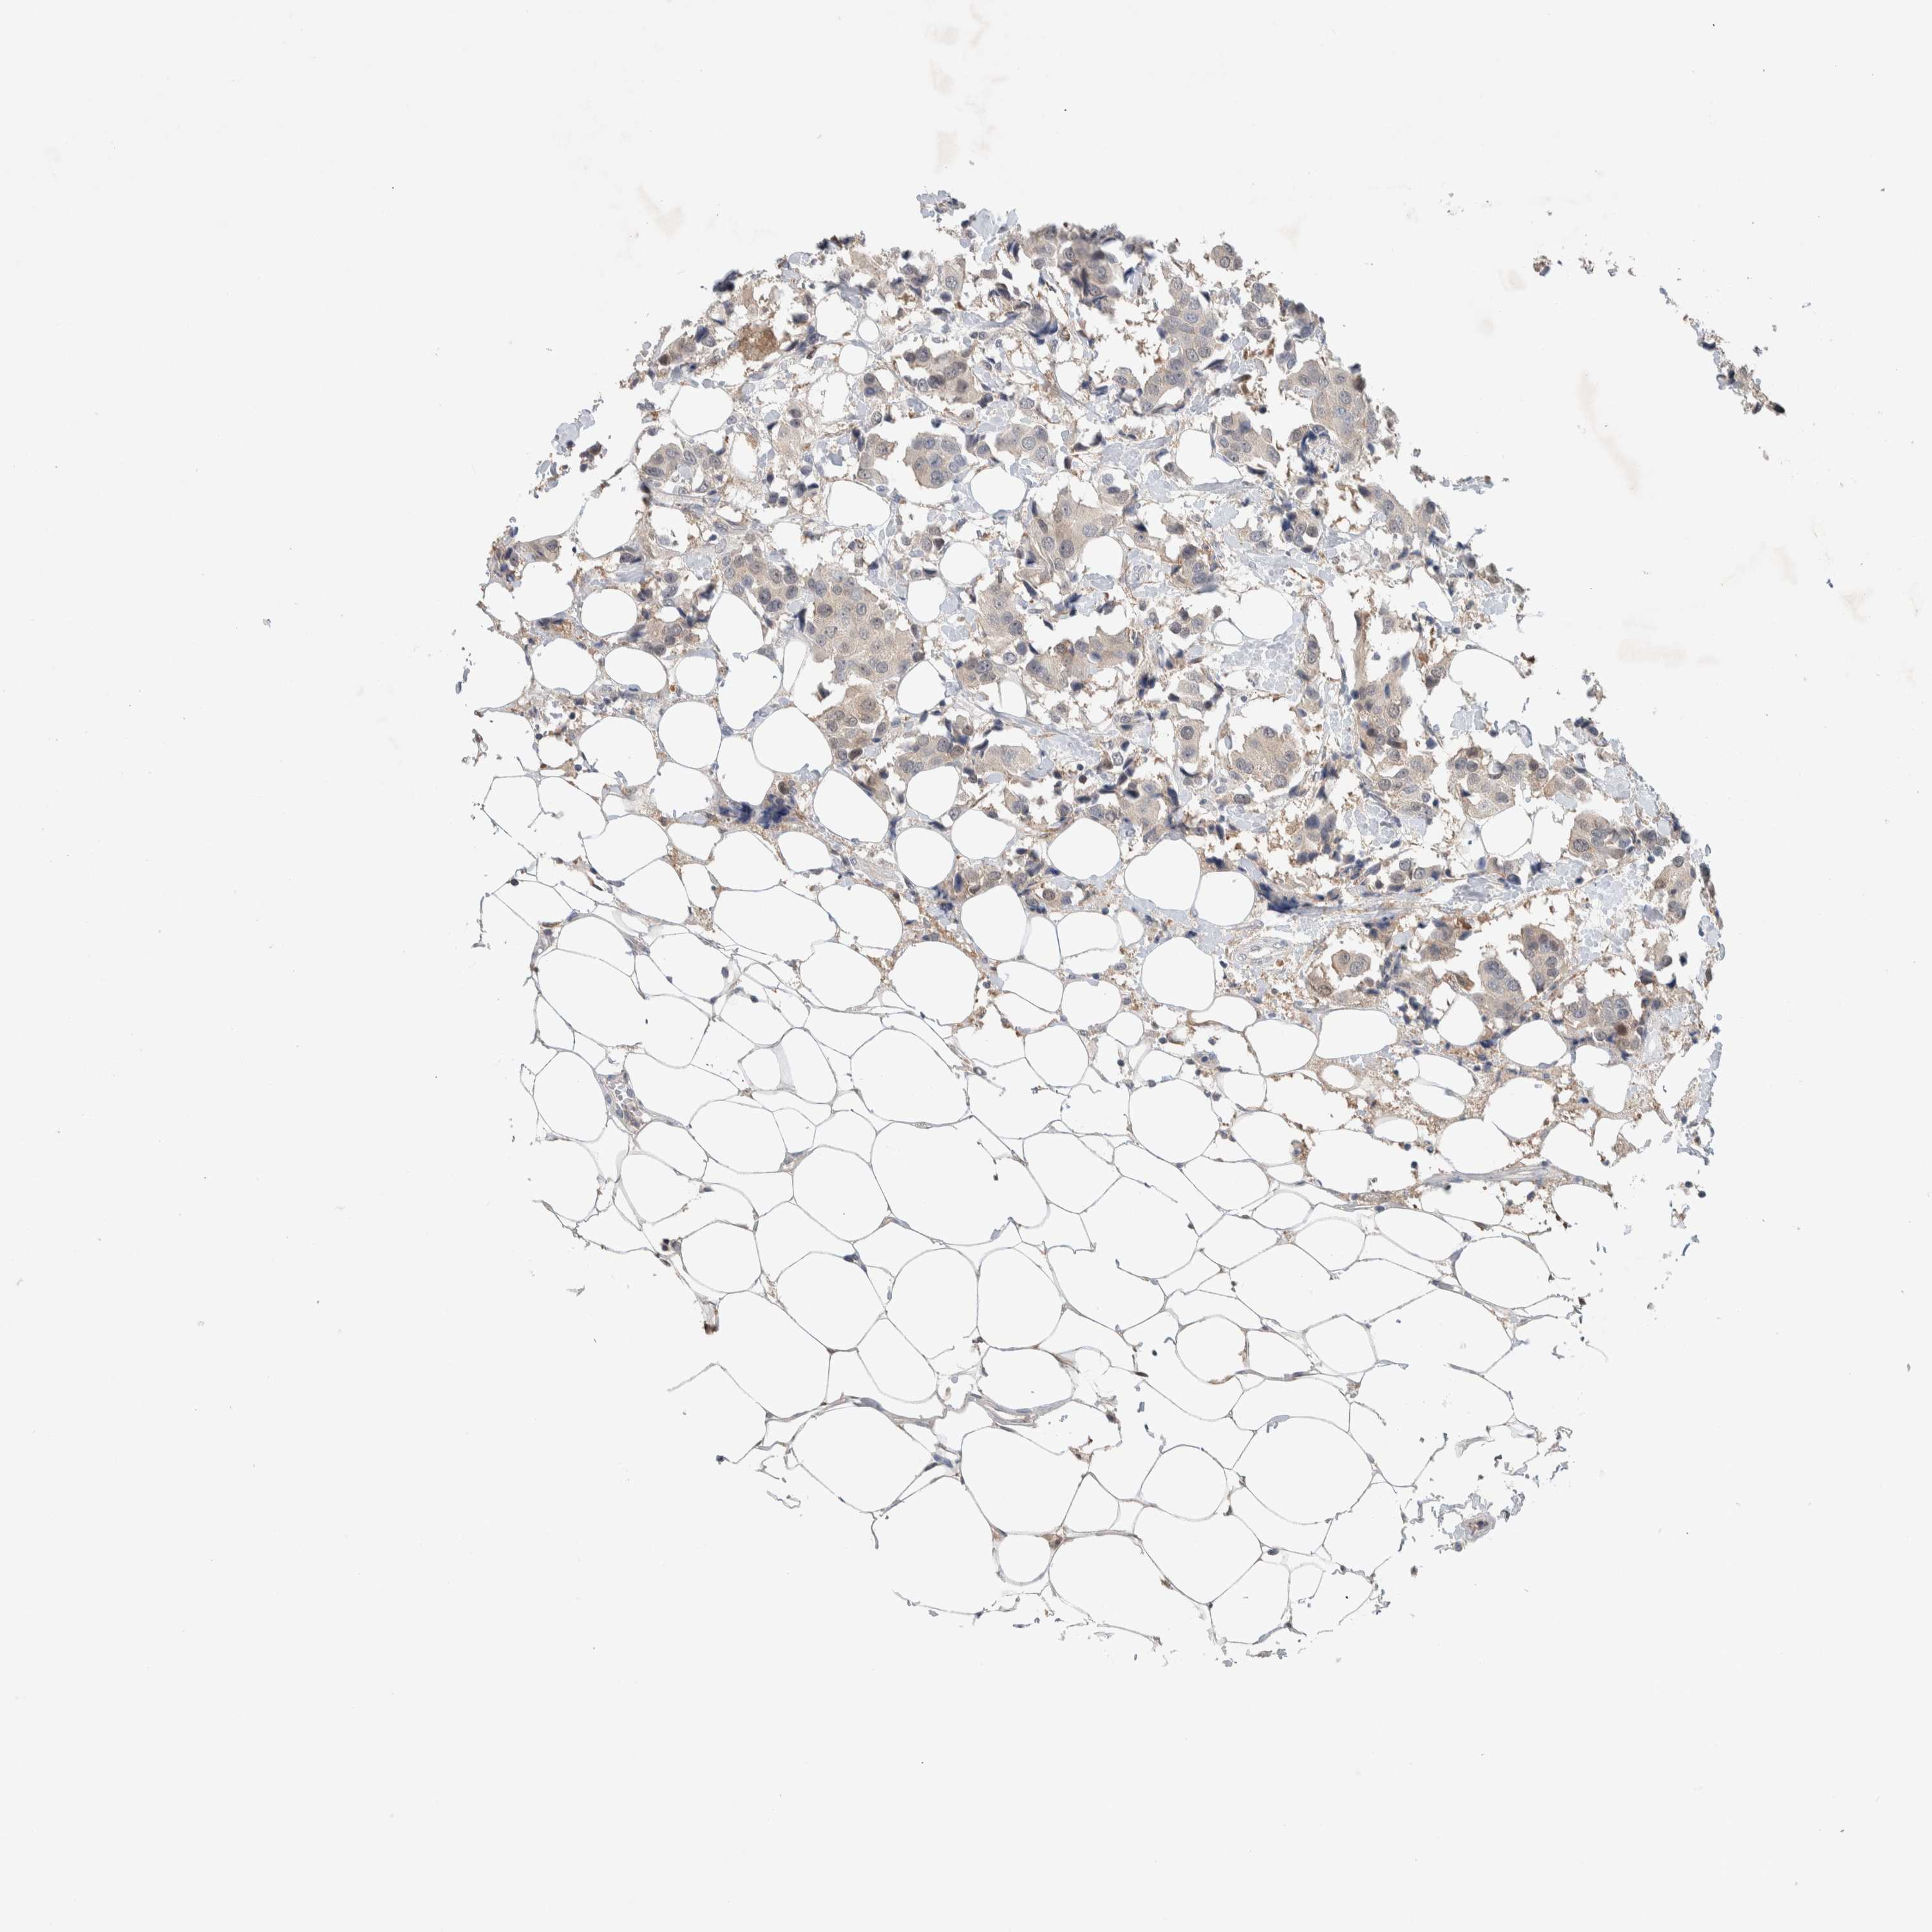

CANCER BREAST CANCER Show tissue menu

BRCA TCGA BRCA VALIDATION PROTEIN EXPRESSION